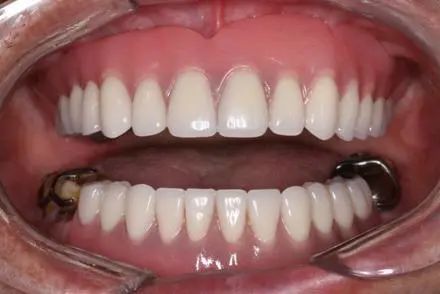

拔除无法保留的牙齿,及时修复缺失牙

老年人如果有无法保留的牙齿应及时拔除,如残留的牙冠、牙根或特别松动的牙齿,否则轻者影响口腔功能,重者引起全身感染,影响生活质量。老年人牙齿缺失后要及时修复,以维持牙列完整,恢复口腔基本功能,一般在拔牙2~3个月后进行修复。修复缺失牙的方法有活动修复、固定修复、种植修复。